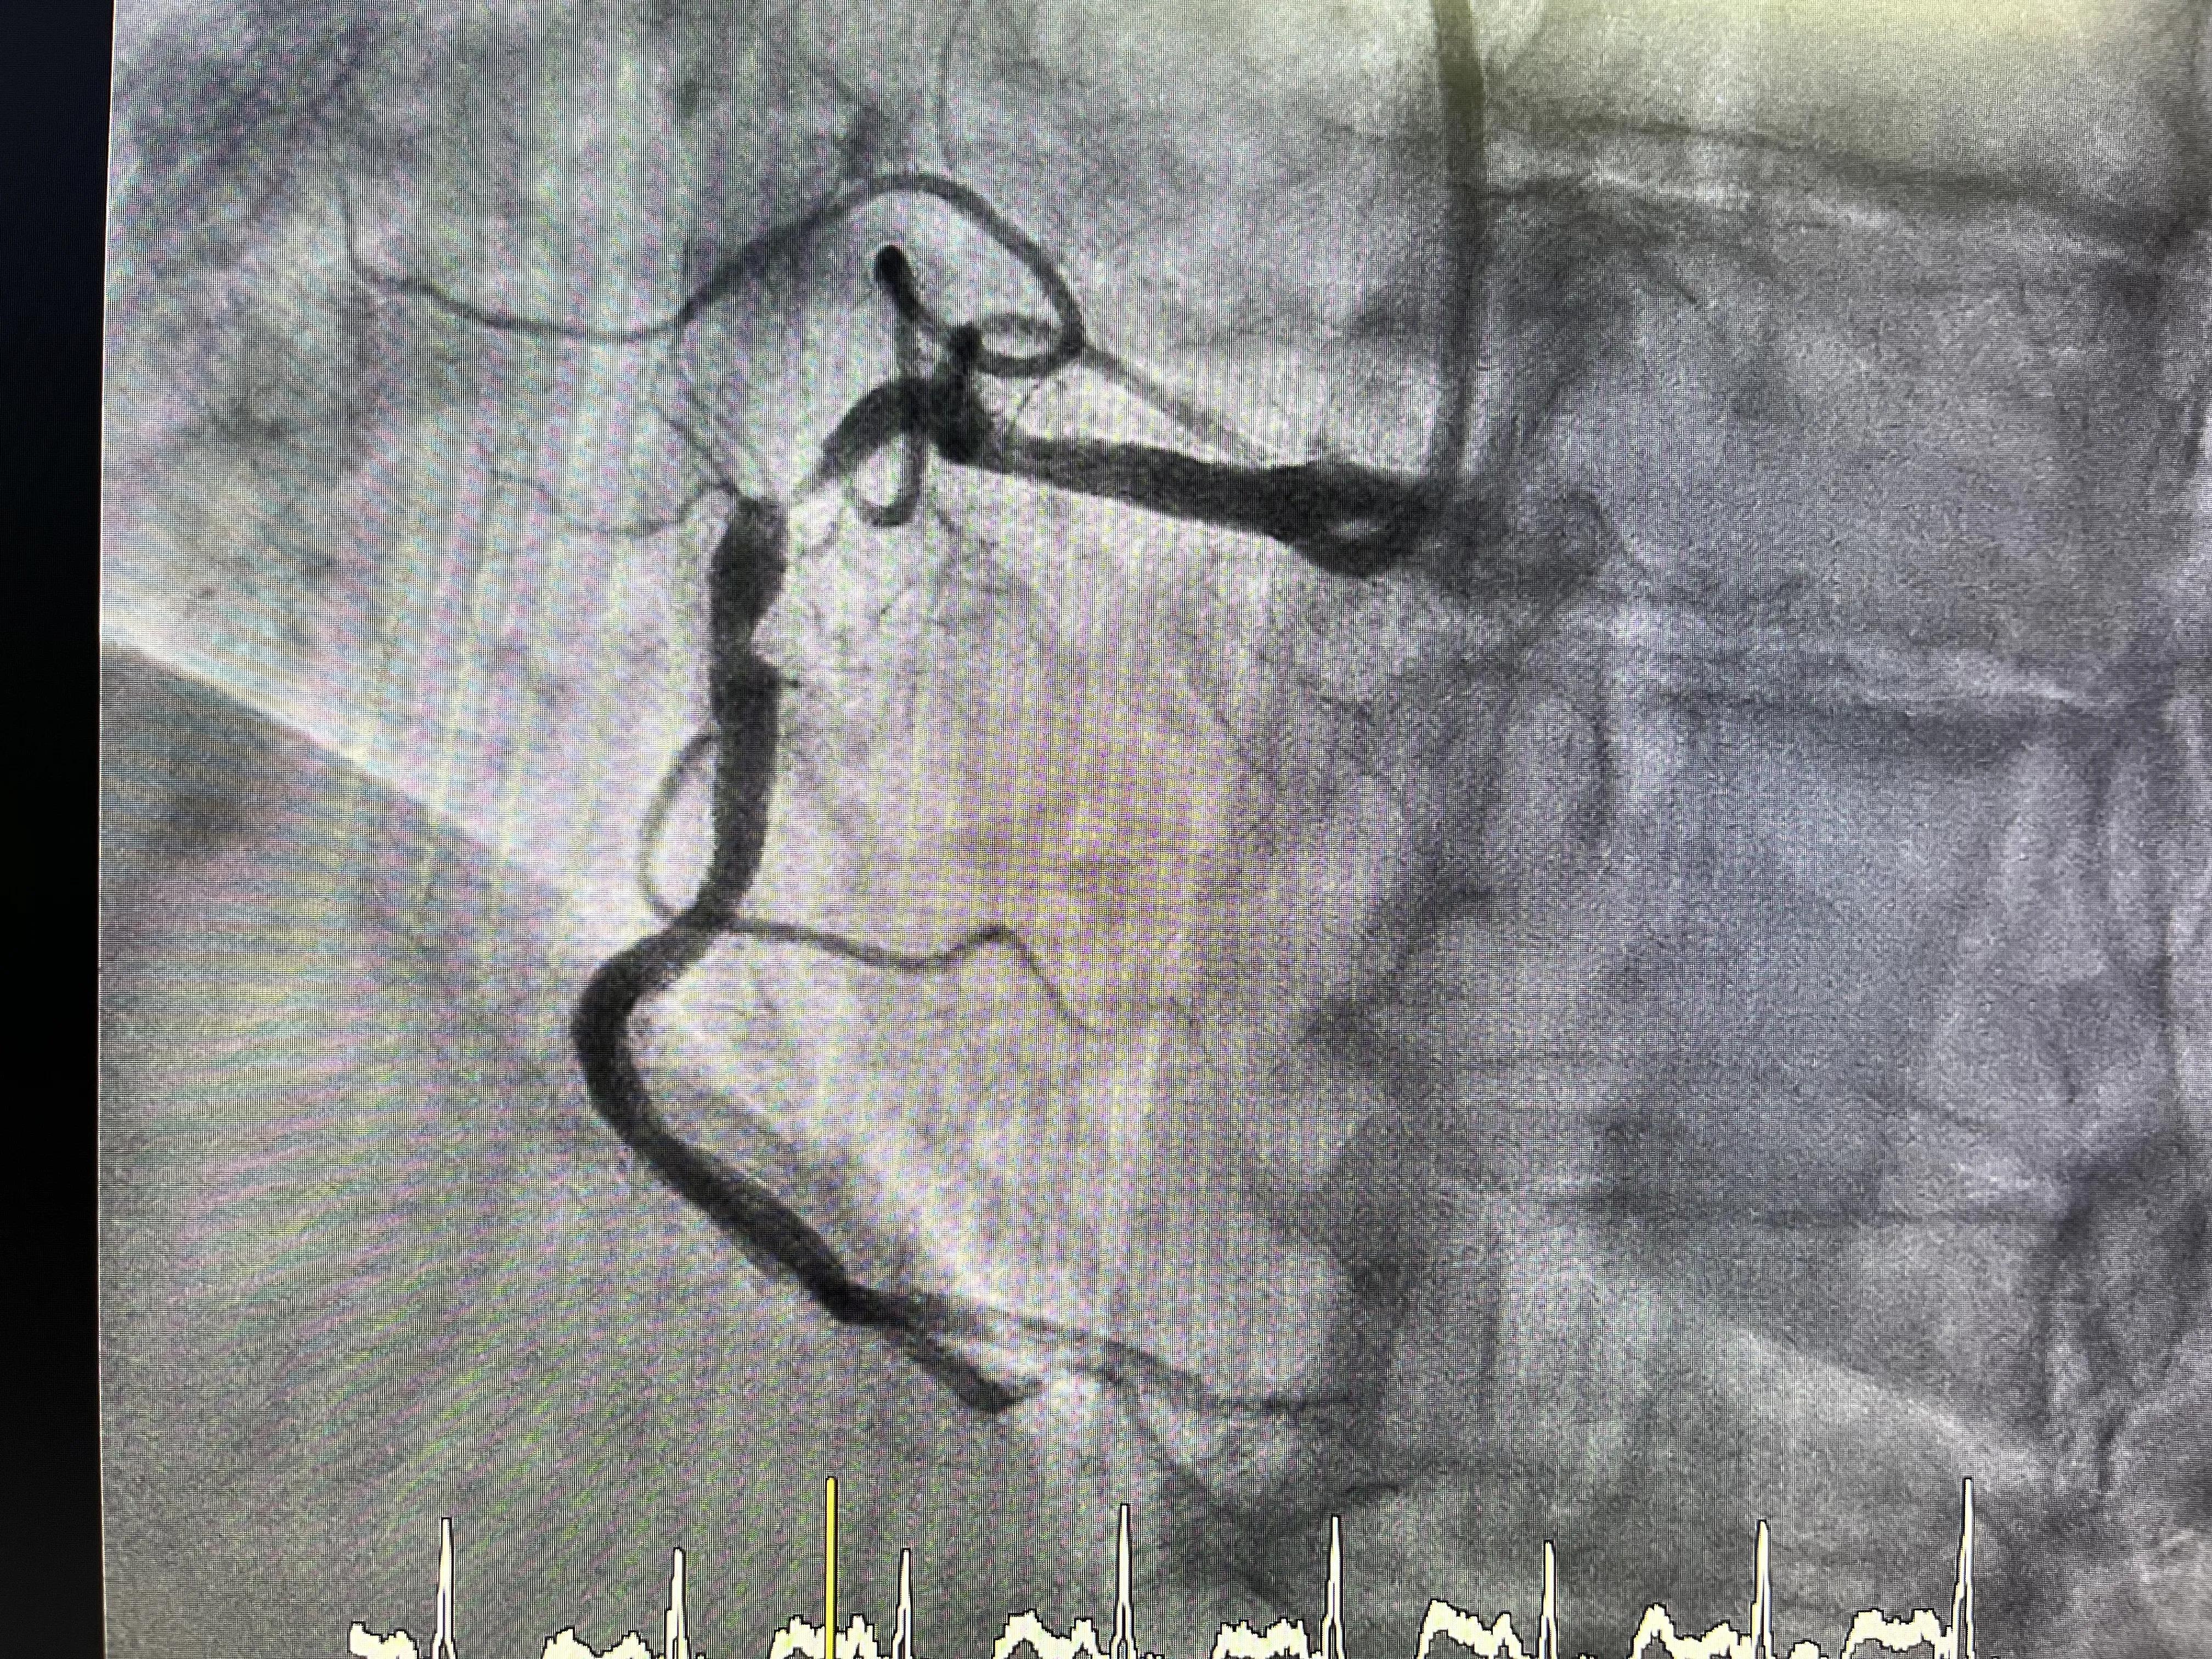

Hallazgo de la coronaria derecha tapada en el caso real

Al canular la coronaria derecha con el catéter guía y realizar la inyección de contraste, se confirmó el hallazgo clave de este caso real: la coronaria derecha estaba claramente tapada. La imagen angiográfica mostraba una oclusión que explicaba de forma directa el infarto inferior que presentaba el paciente. Esta correlación entre clínica, electrocardiograma y angiografía es la que da coherencia a todo el proceso diagnóstico y terapéutico. Ver la arteria ocluida permite además planificar con precisión la estrategia de recanalización.

La visualización de la coronaria derecha tapada marca el punto de inflexión en el procedimiento, pasando de una fase puramente diagnóstica a una fase claramente intervencionista. A partir de ese momento, el objetivo es restablecer el flujo coronario lo antes posible mediante una técnica de angioplastia. La oclusión obliga a trabajar con cuidado en el paso de la guía, ya que el trayecto no está claramente delineado por el contraste. Sin embargo, el hecho de que el resto del procedimiento se desarrolle sin incidencias indica que la anatomía, aunque ocluida, era abordable con las herramientas habituales.